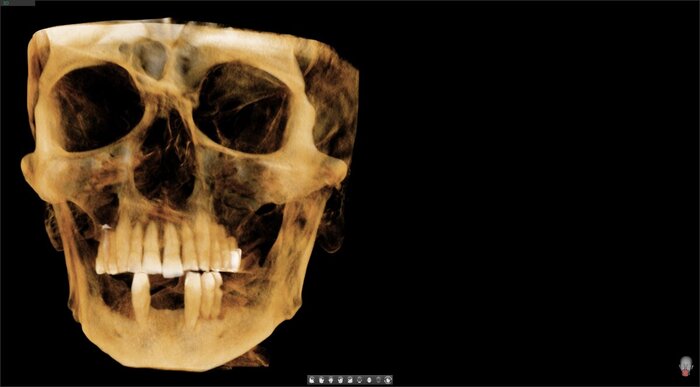

Пока верх не закончен, можно переходить к низу. Тут всё проще (как это часто и бывает). Выбор сделан в пользу тотальной работы на 6 имплантатах (сверху, по итогу, будет то же самое).

Почему? Потому что детская мечта быть роботом понемногу сбывается - на нижней челюсти вместо своих 4-х зубов теперь 6 титановых болтов - имплантатов. И протез.

Да и смысл добавлять скан - всё видно и понятно. На нижней челюсти 4 зуба, которые никуда не годятся.

Изначально планировалось провести работу на имплантатах Неодент. Но позже, пораздумав, имплантолог решил внести коррективы - имплантатов стало не 5, а 6. Неодент заменили на Осстем. Пациенту всё рассказали, всё одобрил. Так удалось сделать идеальную постановку для этого конкретного случая лечения.